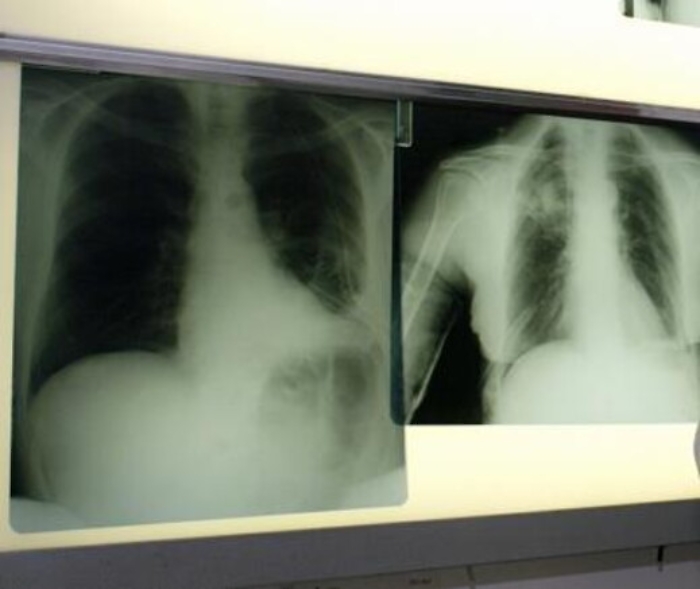

polmoni_esami_fg_1619491904579

Chicago, 6 giu. (AdnKronos Salute) - Una ‘bomba intelligente’, un nuovo farmaco a bersaglio molecolare, sbarra la strada al cancro del polmone che colpisce i non fumatori. E' quanto emerge da uno studio presentato al 52.esimo congresso della Societa' americana di oncologia clinica (Asco), in corso a Chicago. Per i tumori dei non fumatori, che rappresentano circa il 10 per cento dei tumori ai polmoni, lo studio J-Alex ha dimostrato che alectinib, farmaco a bersaglio molecolare è in grado di ridurre del 66% il rischio di peggioramento della malattia rispetto alla terapia standard già utilizzata. “Se finora con i farmaci a disposizione dopo circa 10 mesi non osservavamo più risultati, con il nuovo farmaco - commenta Marina Garassino, Responsabile Oncologia Toraco Polmonare del Dipartimento Medicina Oncologica della Fondazione IRCCS Istituto Nazionale dei Tumori di Milano - dopo quasi due anni 1 paziente su 2 sta bene, la malattia non progredisce e non si verifica nessun effetto collaterale”. Il farmaco ha già ricevuto l'approvazione accelerata dalla Food and Drug Administration (Fda) lo scorso dicembre per il trattamento di pazienti che abbiano avuto una progressione della malattia con la terapia standard a base di crizotinib o siano intolleranti a questo farmaco. Con l’obiettivo di ottenere la piena approvazione come trattamento di prima linea, è attualmente in corso lo studio Alex. “In Italia si stimano 41.000 nuovi casi all’anno di tumore al polmone e di questi, in circa il 6%, è presente un’alterazione denominata ALK”, – continua l’esperta. “Questa alterazione genetica conferisce una particolare sensibilità delle cellule tumorali agli ALK inibitori, di cui crizotinib è stato il pioniere e rappresenta attualmente il trattamento standard per questi pazienti. I dati ci dicono che alectinib è molto superiore a crizotinib nel controllo della malattia e con una tollerabilità nettamente superiore. Ciò significa che alectinib sarà importante perché permetterà ai pazienti di cronicizzare la malattia solo con una pastiglia al giorno, per via orale e salvaguardare, quanto è possibile, la loro qualità di vita. Attualmente, i risultati riguardano la popolazione asiatica, ma speriamo si confermino anche nella popolazione occidentale.” "Questo è il primo studio che dimostra come alectinib aiuti i pazienti a vivere più a lungo, ritardando la progressione della malattia, rispetto a crizotinib", ha spiegato Sandra Horning, MD, Chief Medical Officer e Head of Global Product Development di Roche. "Crediamo che questi risultati, in termini di efficacia e sicurezza, rappresentino un significativo passo avanti per i pazienti con cancro del polmone ALK-positivo; naturalmente sottoporremo questi dati alla Food and Drug Administration americana e ad altre autorità regolatorie".